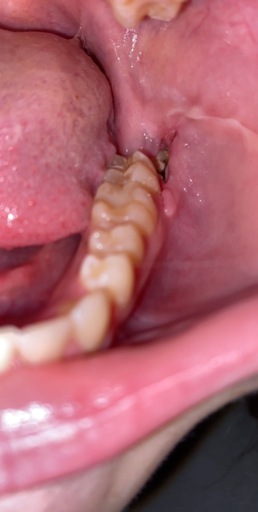

Is the a dry socket or normal healing?

got pulled 3 days ago curious whether or not it’s a dry socket isn’t into much pain I would really appreciate if someone would answer. feels normal just wondering has stitches around it. not to deep of a hole.